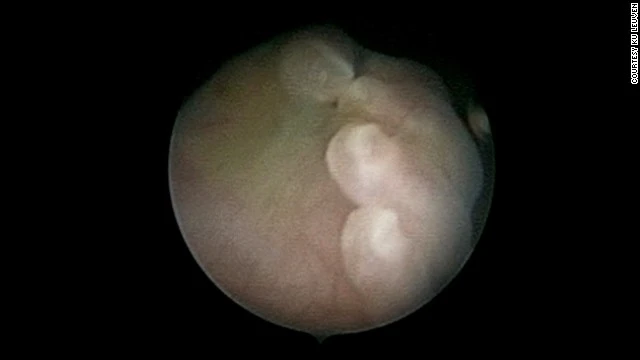

Thiết bị này bao gồm một máy camera cung cấp hình ảnh 3D của bào thai, giúp 2 cánh tay linh động có thể thực hiện thao tác tại xương sống của trẻ trong bụng mẹ. Nếu thành công, cánh tay này sẽ có thể phát triển để thực hiện kỹ thuật phức tạp hơn như phẫu thuật tim. Chúng cũng có thể thực hiện các hoạt động khác với các tế bào gốc trong cơ thể. Do đó, chỉ cần kỹ thuật phẫu thuật trong bào thai thành công, tiềm năng ứng dụng của cánh tay rô bốt là rất lớn.

Cánh tay của thai nhi qua hình ảnh 3D của rô bốt.